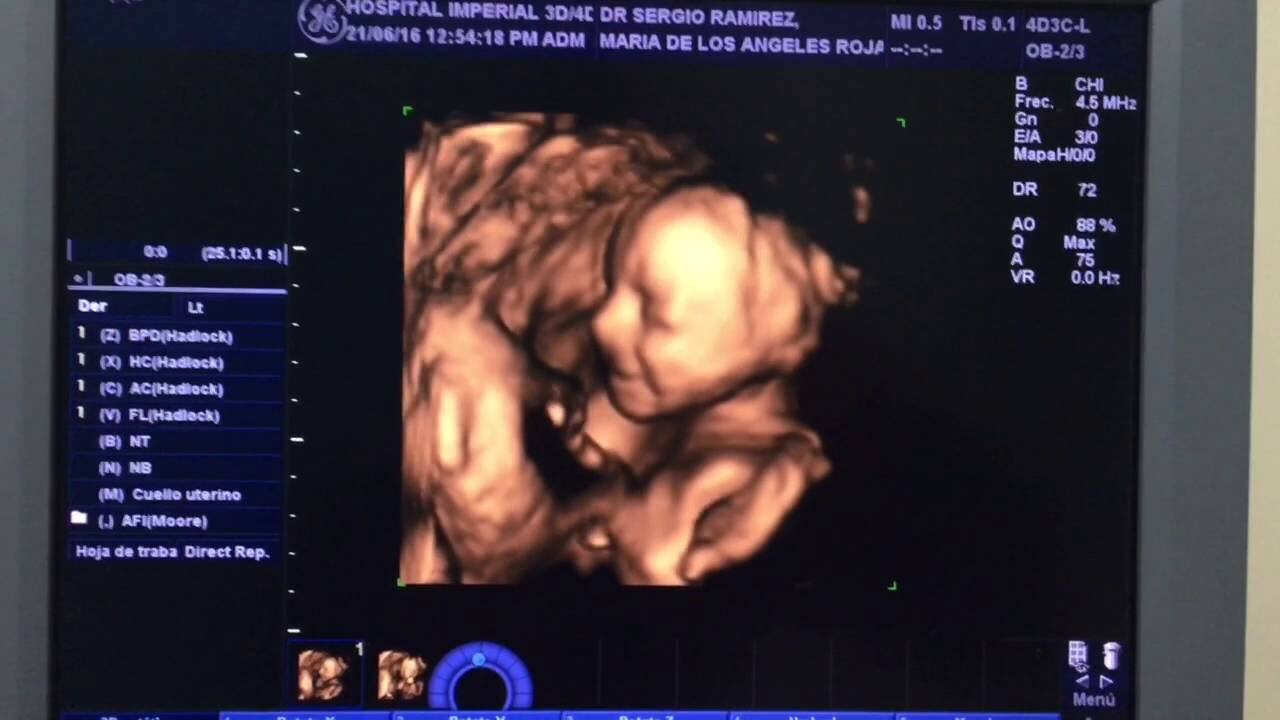

Haz una elección “mucho más consciente” Marca el final de otra técnica "complementaria" a los tres métodos de ultrasonido tradicionales, como la ecografía 4D, que permite a los padres ver el vídeo "en tiempo real" con "la cabeza, las manos, los pies o los dedos de la niña embarazada".

ultrasonido 4D

En cuanto a la ecografía 4D, es una tecnología de ultrasonido adicional y no un sustituto de los exámenes de ultrasonido estandarizados para monitorear el embarazo, que "posiblemente ofrecen ventajas para la valoración ecográfica de los profesionales", ya que “permite una mejor visualización del feto así como una mejor valoración del corazón, lo que permite detectar antes las cardiopatías congénitas”.